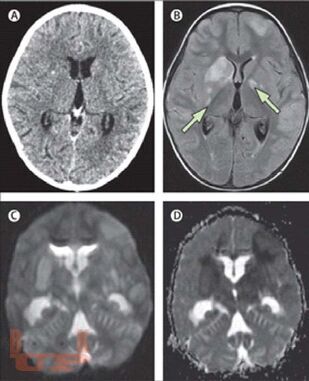

В предлагаемом учебном пособии рассматриваются вопросы патогенеза, патологической анатомии, диагностики, дифференциальной диагностики, лечения туберкулеза центральной нервной системы у детей и взрослых.